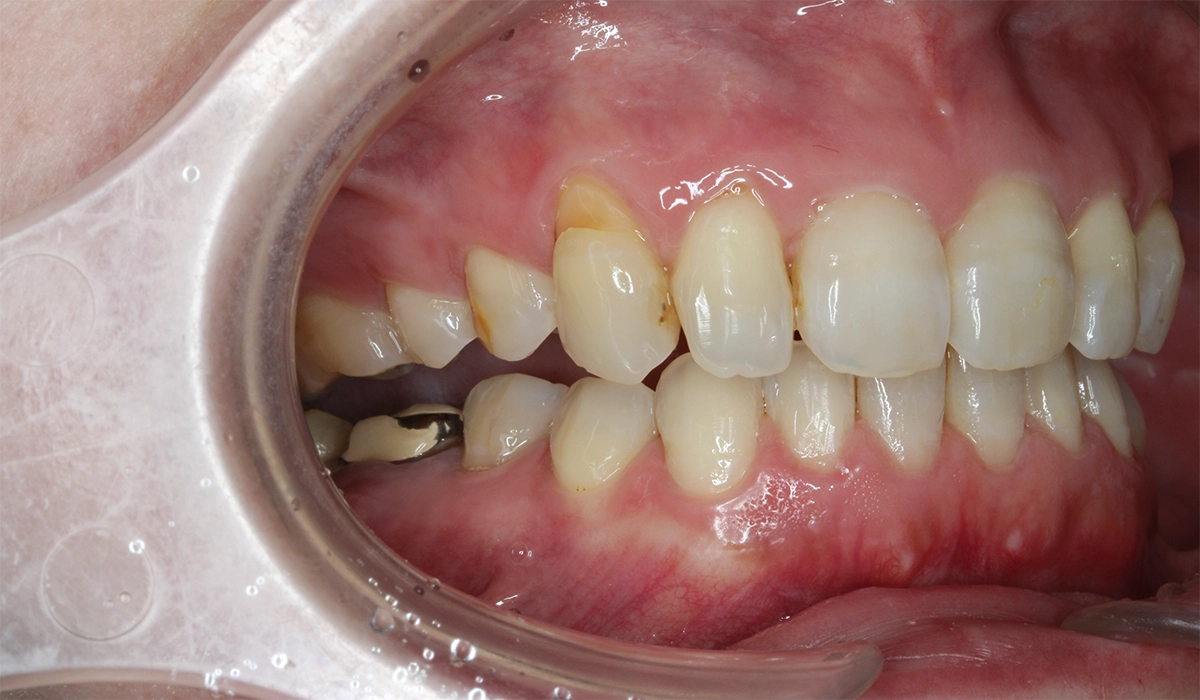

術後:左側